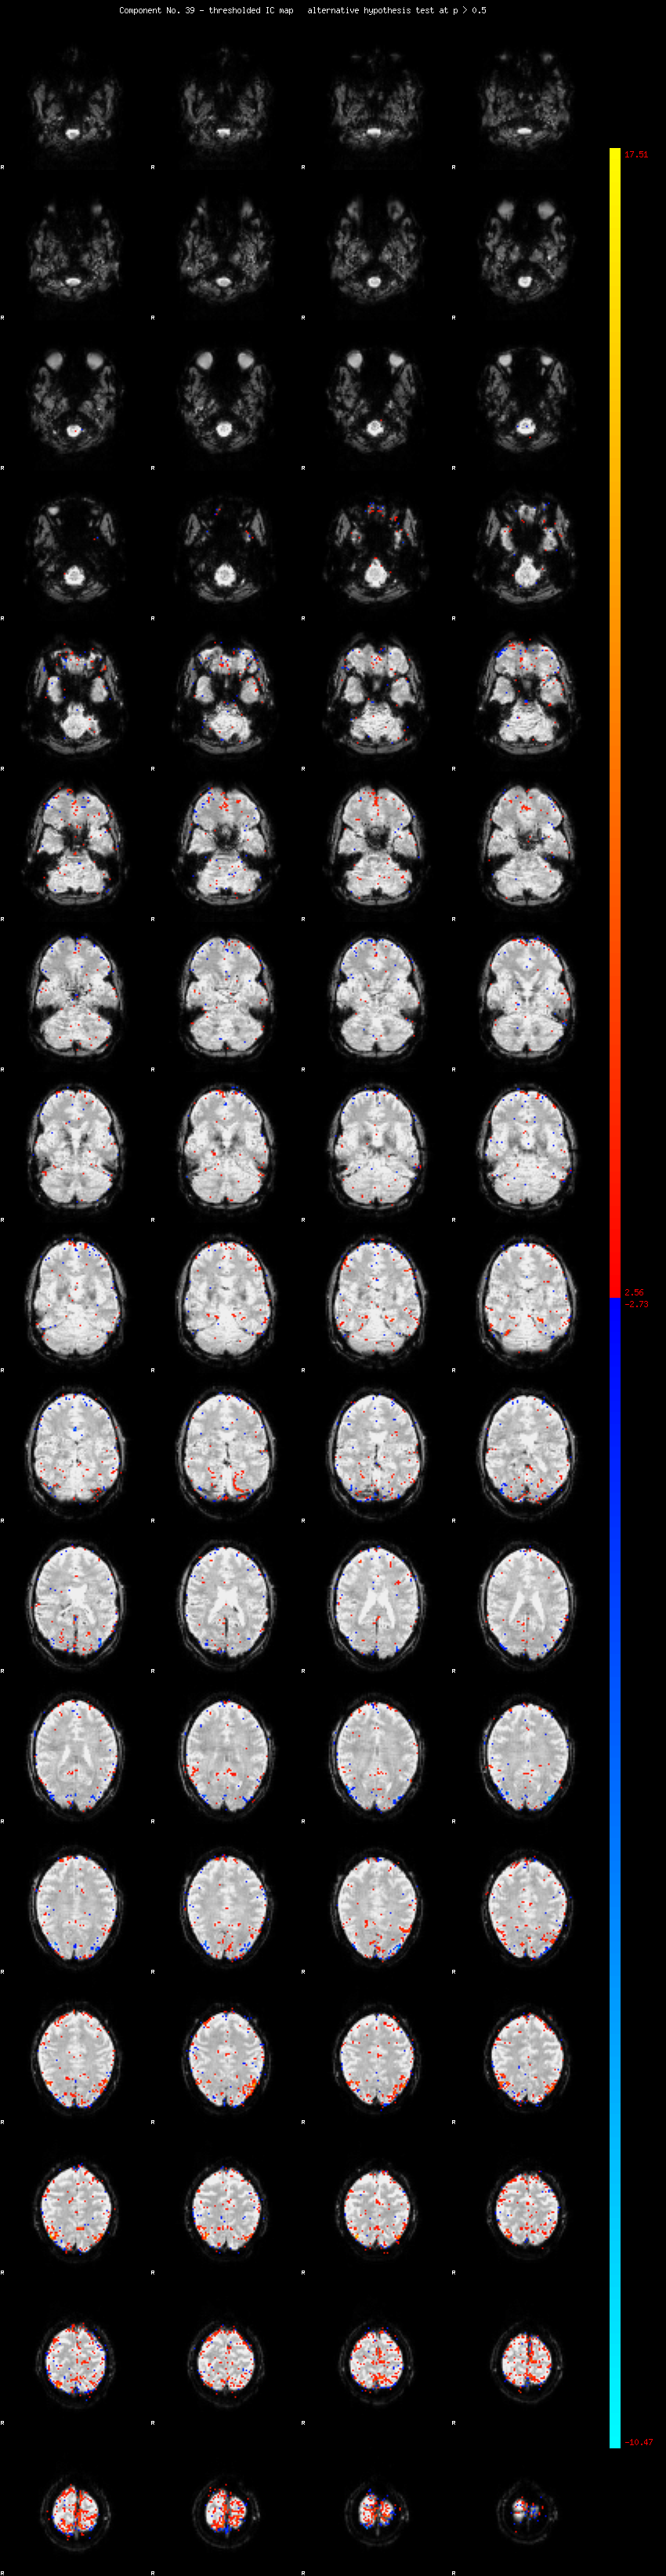

MELODIC Component 39

1.11 % of explained variance;     0.74 % of total variance

MMfit